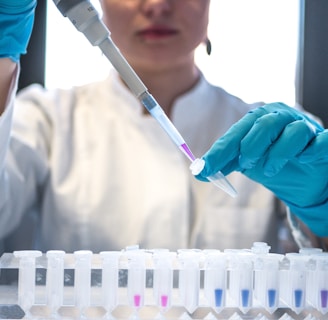

🔬 Advanced Diagnostic Services

Accurate diagnosis for effective treatment

Comprehensive blood work and lab testing

Are lab tests onsite?

Yes, our clinic offers convenient on-site laboratory services for blood tests.

Where expert doctors and lab services come together seamlessly.